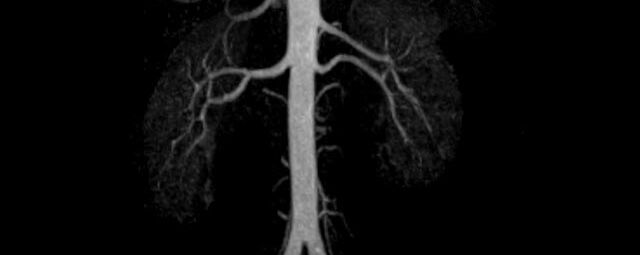

Aorta

• Bauchgefäße

• Erfassung und Verlaufskontrolle bei arteriellen Aneurysmen (Aussackungen der Arterien), vor allem der Bauchaorta

• Darstellung von Gefäßengen an Nierenarterien, Baucharterien und Becken-/Beinarterien

MR-Angiografie (MRA)

Ganzkörper Angiographie mit Kontrastmittel

• MR-Angiographie mit Kontrastmittel

• Erfassung arterieller und venöser Gefäße/Bypässe aller Körperregionen mit 3D-Rekonstruktion

• je nach klinischer Fragestellung zeitaufgelöste MR-Angiographie (4D-MRA) z.B. bei Frage arteriovenöse Fistel/ Shunt oder Darstellung Unterschenkelarterien vor geplanter Bypassoperation.